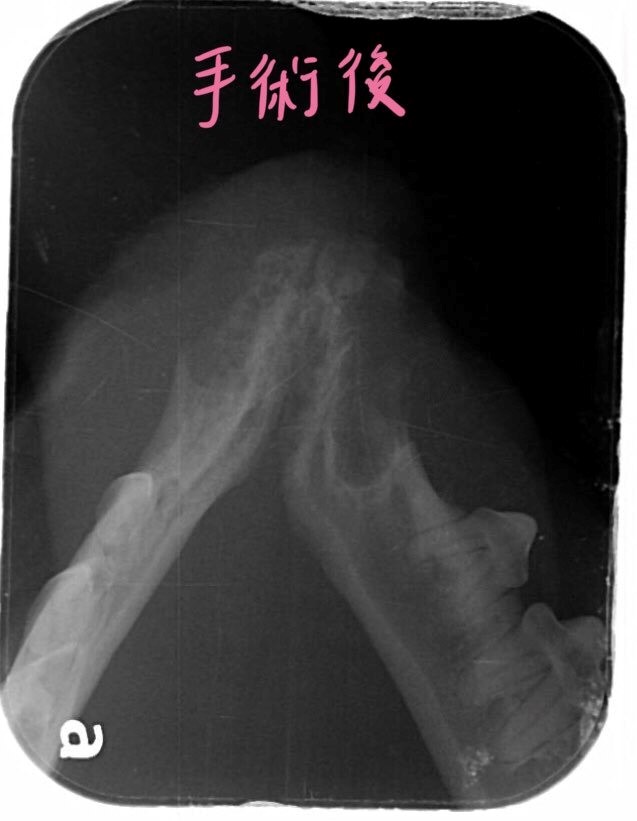

將這些發育異常且已感染的牙齒移除

術後一個月回診牙齦腫脹消失,食慾良好,體重也變胖了一些